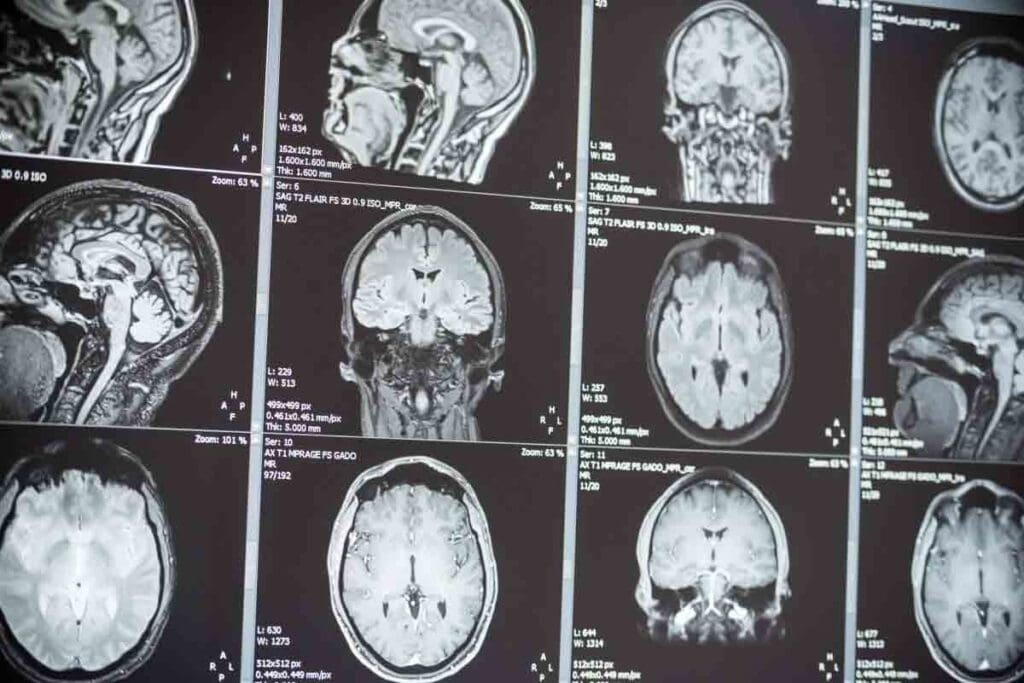

Brain tumors affect people of all age groups. But how often they happen and how well people survive varies a lot. Knowing these differences helps patients, families, and doctors make better choices.

It’s important to know how brain tumors affect Americans. These tumors, both cancerous and non-cancerous, are a big health problem in the US.